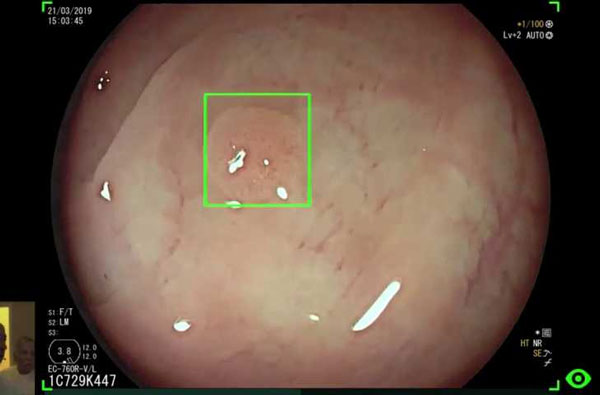

Yapay zekanın kolon taramasında çok katkısı olduğuna dikkat çeken Çekin, “Polip dediğimiz, kolonda bulunan ve istenmeyen yapıları alarak ileride bu kişilerin kolon kanserine yakalanmasını engelleyebiliyoruz. Bu poliplerin taranmasında yapay zeka uygulaması gündemde ve şuan biz bunları kullanıyoruz. Kolonoskopist, kolonda ilerlerken, yapay zeka polip gördüğü zaman hem sesli hem görsel olarak ışık yakarak kolonoskopisti uyarıyor. Bunlar küçük poliplerde çok önemli.

Çünkü gözden kaçabiliyor ya da arkalara saklanabiliyorlar. Bu da endoskopistin dikkatini çekmeyebilir. Yapay zeka uygulamaları bunları uyararak bilgilendiriyor ve işlemin kalitesini oldukça fazla arttırıyor. Yapay zeka, deneyimli gastroenterologlardan daha iyi değil ama polip yakalamada deneyimsiz, endoskopiyi yeni öğrenen arkadaşlardan daha iyi” dedi.

Endoskopik görüntülenmenin teknolojiyle birlikte oldukça geliştiğini ve yapay zekayla birlikte kanserin çok önceden tespit edilebildiğini aktaran Prof. Dr. Çekin, “Artık bize hücre düzeyinde mikroskopik görüntü verilebiliyor. Endoskopla baktığınız zaman, ‘burada kanser olma ihtimali çok yüksek’ diyebiliyorsunuz.

Bunların kayıtlarını değerlendiren yapay zeka, endoskopi sırasında bölgeyi kare içine alarak sıkıntı olduğu uyarısını veriyor. Deneyimli endoskopistlerle karşılaştırıyorlar yapay zekayı ama hala biz iyiyiz. Ancak teknoloji ilerledikçe, yapay zeka bizimle eşdeğer olacak. Biz yüzde 95’iz, onlar yüzde 93. Çok az fark var arada. Önümüzdeki günlerde muhtemelen polip uygulamasının dışında yemek borusu ve mide kanserlerinin tespitinde de uygulamaya girecek” diye konuştu.